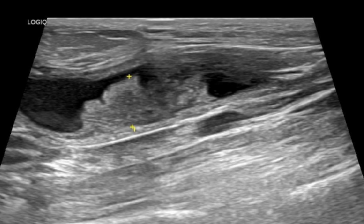

강아지 방광암 / 출처 ㅣ 에스동물암센터

강아지 방광암, 요도폐색 (출처 ㅣ canna-pet.com)